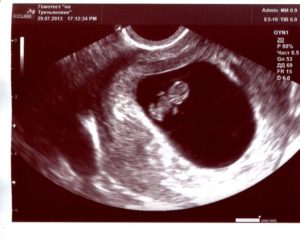

- УЗИ, определяет 8 недель беременности размер плода, состояние кровоснабжения, плаценты и т.д.;

После того как вы сообщите врачу о тревожащих вас симптомах, он назначит вам ультразвуковое исследование. Специалист, который будет делать УЗИ, сможет определить состояние плода, стенок матки. Кроме того, можно определить локализацию спазма, так, он может локализоваться на задней стенке. Не менее часто встречается гипертонус передней стенки.

Для диагностики гипертонуса используется ультразвуковое исследование, при проведении которого может быть выявлен гипертонус задней стенки матки, а также передней. Однако, этот признак не всегда может говорить об угрозе прерывание беременности. Матка может прийти в тонус в ответ на прохождение ультразвуковой волны через ее стенку.